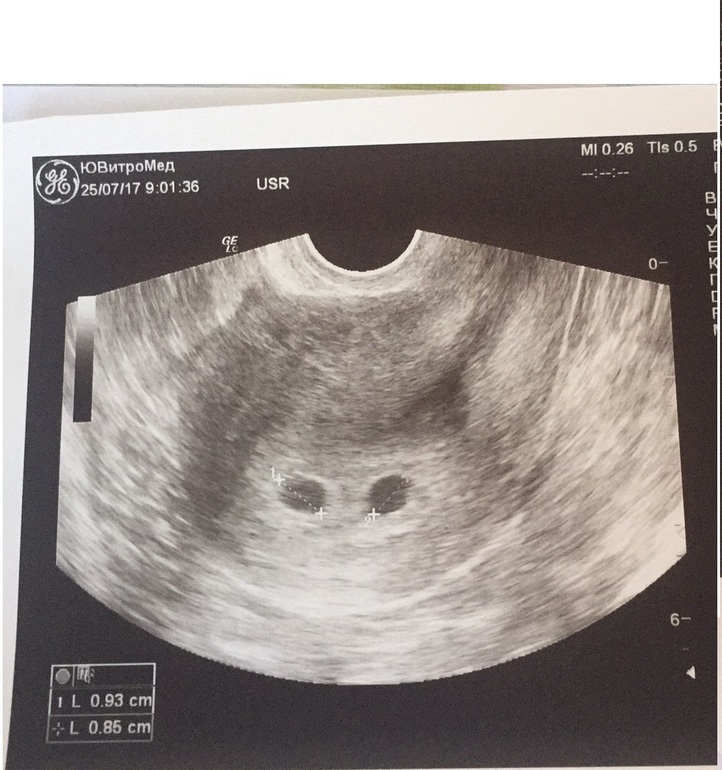

УЗИ двухплодной беременности на 5 неделе: Подборка изображений

Раздел: Калейдоскоп образов